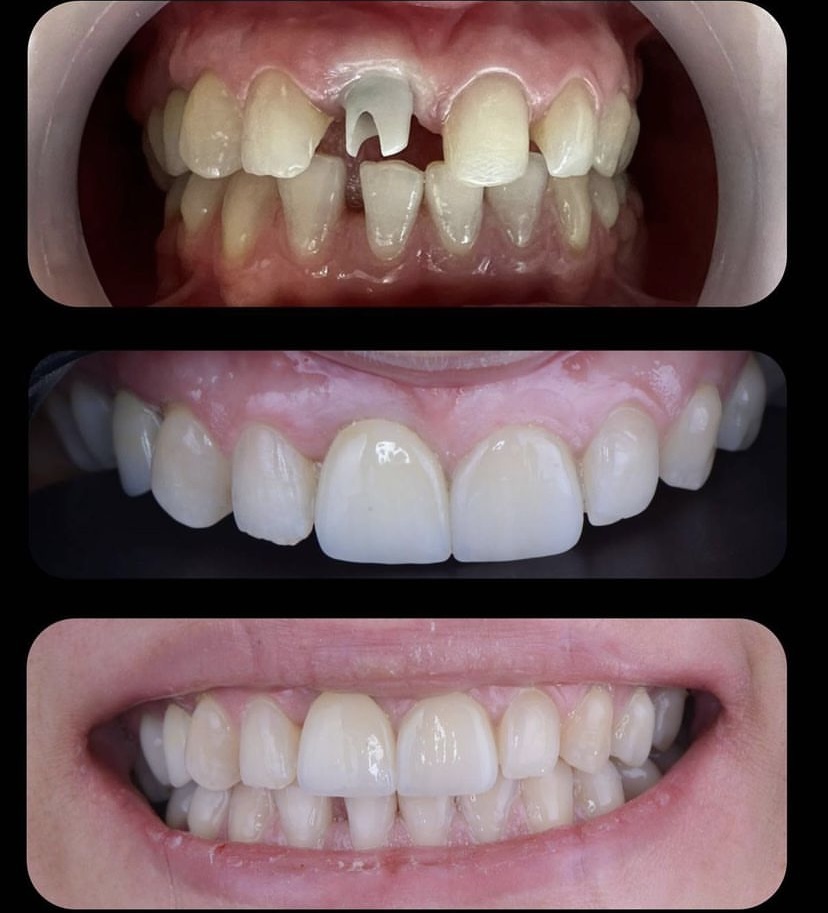

Öncesi̇-Sonrası Resi̇mler

Galeri Öncesi̇-Sonrası Resi̇mler